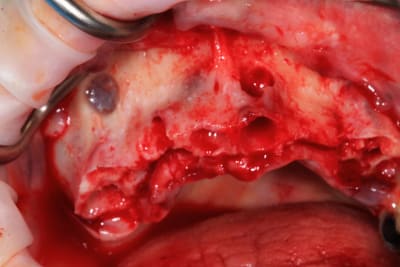

Guide métal avec support clavette, os assez fin : il est prévu un sticky bone complet : donc : lambeau avant extraction, positionnement du guide base et forage des clavettes, positionnement du guide implant, pose des piliers MU, controle des axes prothétique avec le guide pilier, collage des piliers prov sur le bridge a armature métal, occlusion nickel, sticky bone et PRF, sutures suspendues.

Voilà les photos du cas , avec un peu de retard.

Enfin, le cas de la semaine précedente. Guide osseux maison, bridge imprimé. On conserve 26 27. Mais les sinus sont assez antérieurs : on sort au niveau des 4 avec les implants angulés. Malgré le fait de faire un mini comblement sinus droit : l'implant passe la crete, rentre dans le sinus, et retrouve l'os en direction nasal, mais on sort quand meme en 14.

Alors pose d'un implant dans l'alvéole de la 15, aucune stabilité, comblement. A utiliser pour le bridge définitf.